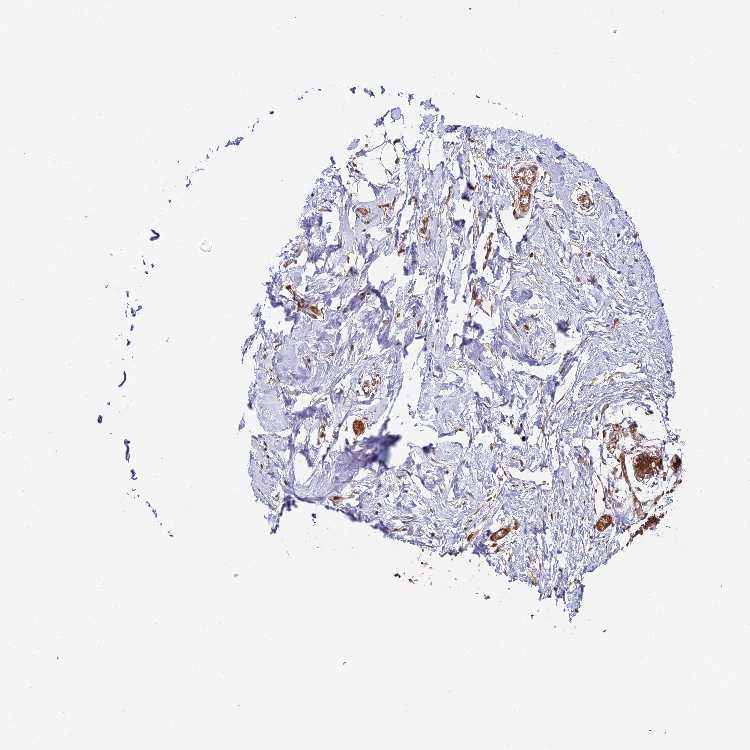

BREAST - Antibody stainingi

Antibody staining in the annotated cell types in the current human tissue is reported as not detected, low, medium, or high, based on conventional immunohistochemistry profiling in selected tissues. This score is based on the combination of the staining intensity and fraction of stained cells.

Each image is clickable and will lead to virtual microscopy that enables deeper exploration of all samples and also displays staining intensity scores, fraction scores and subcellular localization as well as patient and tissue information for each sample.

Antibody HPA042996Antibody HPA045576Antibody HPA049949

Adipocytes LowNot detectedNot detected

Glandular cells MediumHighMedium

Myoepithelial cells MediumLowMedium